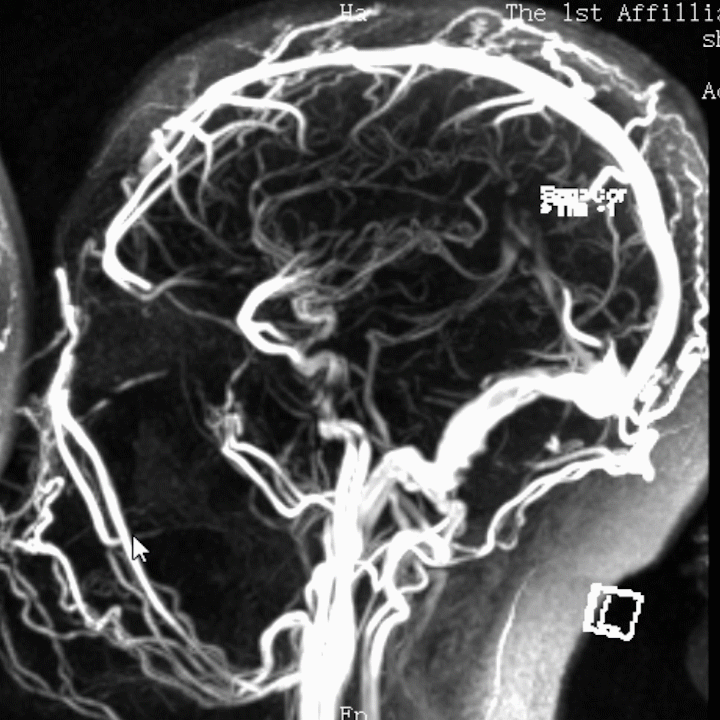

股动脉入路动脉造影显示上矢状窦后部和左侧横窦不显影,静脉期显影延迟,皮层静脉开放并明显增粗; 股静脉入路超选颅内静脉,微导丝和微导管引导ACE抽吸导管超选颅内静脉窦造影显示上矢状窦后部和左侧横窦内血栓影。

在静脉窦内造影显示血栓负荷量明显减少,静脉窦再通, 再次动脉造影显示静脉窦内血流恢复,窦内血流稍慢。

术后第6天复查动脉造影,计划必要时调整溶栓导管位置,显示静脉窦内血栓完全消失,遂拔出导管和鞘管。

6月随访患者未诉不适,MRS 0分,复查MRV见静脉窦再通良好。